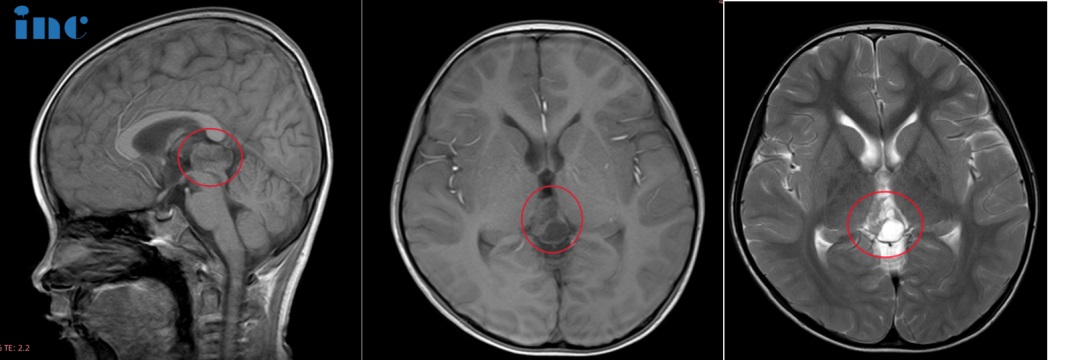

影像特征

12岁儿童,矢状位T1WI示松果体区低信号肿块,横断位T2WI示一高信号肿块右份伴局灶性低信号,代表钙化,注意与病灶相关的脑积水;横断位及矢状位T1WI+C示明显强化肿块